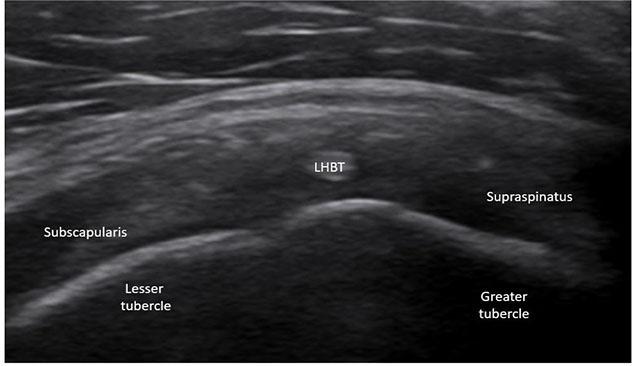

Among the 3,600 shoulder ultrasound examinations, 23 cases were initially suspected of AEST pathology. After detailed review, four cases were excluded: one due to a thin hyperechoic fibrous band within a degenerative LHBT mimicking a bifid tendon (Fig. 5), two cases in which normally echogenic fibers were preserved despite advanced LHBT degeneration (Fig. 6), and one case of hypoplastic LHBT (Fig. 7).

Pseudo-double long head of the biceps tendon (LHBT). A. Longitudinal view mimicking a bifid tendon. B. Transverse view showing a narrow intratendinous fibrous band accentuated by degenerative changes